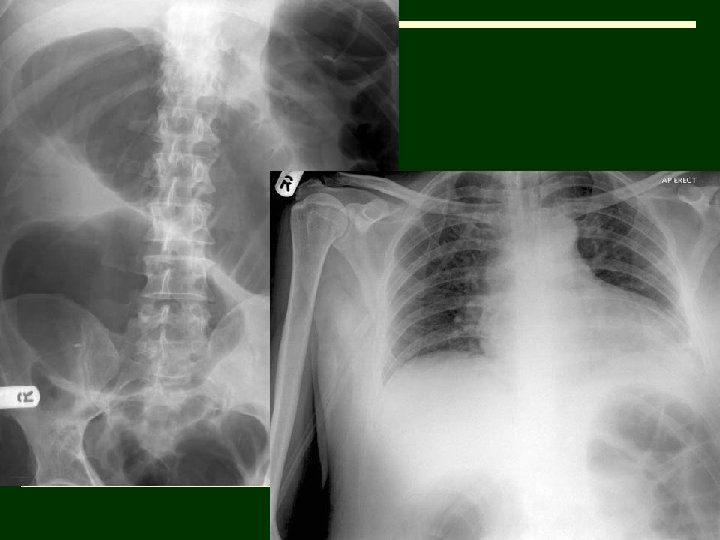

o. Lipohaemarthrosis, fractured neck of humerus

12. o 50 year old man underwent an above-knee amputation to remove his gangrenous leg. He developed nausea and dyspneoa on the 4 th postoperative day. The abdomen, though distended, was not tender and the bowel sounds were audible. Digital rectal examination was unremarkable.

o(A subsequent CT scan of the abdomen did not reveal a mechanical cause of the condition and colonoscopic decompression was therapeutic)

Diagnosis o. Acute colonic pseudo-obstruction or Ogilvie syndrome

Discussion o Acute colonic pseudo-obstruction or Ogilvie syndrome is a condition with clinical and radiological features of colonic obstruction without any evidence of a mechanical cause. o Abdominal distension in this patient accounted for the respiratory distress and the dilated large bowel loops seen on the chest radiographs guided towards the correct diagnosis. o Pathophysiology is not clearly understood, though it is thought to be due to an imbalance in the autonomic innervation leading to a functional bowel obstruction. o Ogilvie syndrome typically occurs in patients hospitalized with a significant illness e. g. severe cardio-respiratory disorders, sepsis, electrolyte imbalance and postoperatively. o Left untreated it can progress to colonic perforation and peritonitis. Plain abdominal film is the initial imaging investigation of choice. Colonoscopy can be both diagnostic and therapeutic

Differential o Mechanical colonic obstruction o Toxic megacolon o Mesenteric ischaemia